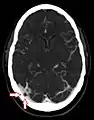

CT angiography showing an arachnoid granulation in the right transverse sinus